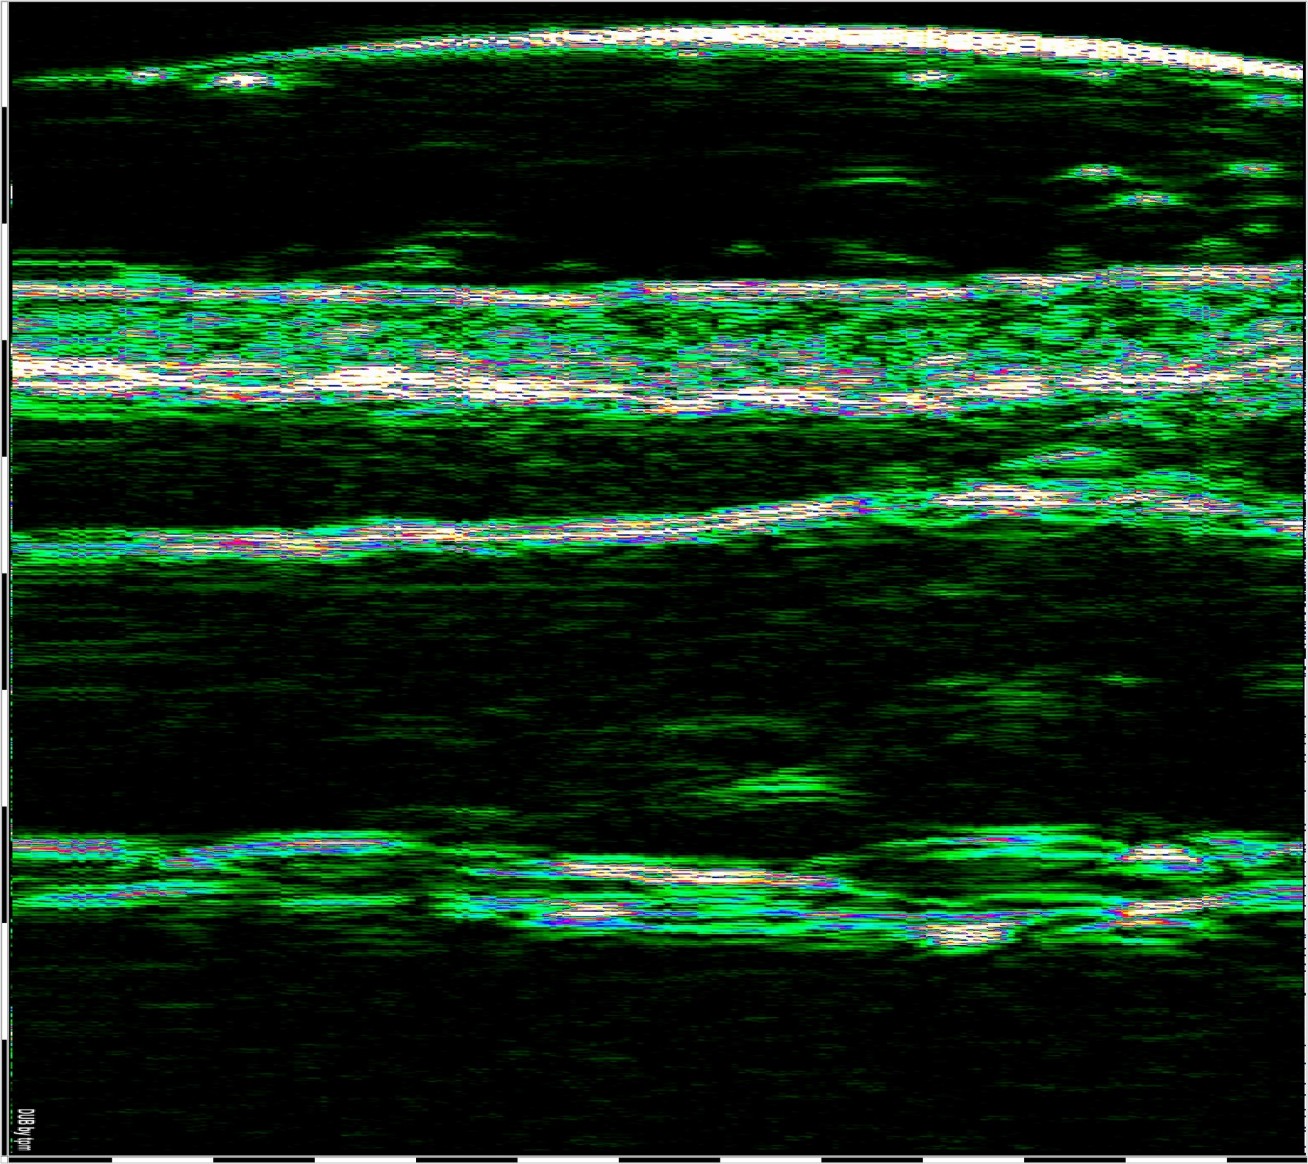

ΣΥΣΧΕΤΙΣΜΟΣ ΜΕΤΑΞΥ ΥΠΕΡΗΧΟΥ ΥΨΗΛΗΣ ΣΥΧΝΟΤΗΤΑΣ ΚΑΙ ΜΙΚΡΟΑΝΑΤΟΜΙΑΣ ΔΕΡΜΑΤΟΣ

Σάρωση άθικτου δέρματος στα 75 MHz (αριστερά) και διάγραμμα της μικροανατομικής δομής του δέρματος (δεξιά).

e – επιδερμίδα, pd – θηλώδες χόριο, rd – δικτυωτό χόριο, hf – θύλακας της τρίχας, bv – αιμοφόρο αγγείο βαθέος δερματικού πλέγματος, λίπος – λιπώδης ιστός, fas – περιτονία, msc – μυς.